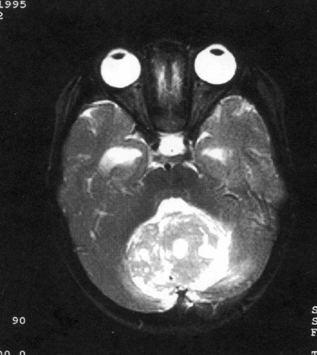

问题 病历摘要:??患儿男性,11岁。半年前开始出现行走不稳,常无故跌倒。半月前出现发作性剧烈头痛,伴恶心呕吐。体检:T36℃,P100次/分,R22次/分,BP100/60mmHg,神清,言语较缓慢,双眼外展约不及边,双眼侧视时有小幅度水平眼震。四肢肌力正常,右上肢肌张力较低,坐位姿势不稳,常不自主摇晃,双上肢指鼻不准,行走蹒跚步态,足距扩大,身前倾。 患儿目前出现了哪些方面的临床症状

选项 A.颅内压增高表现 B.小脑蚓部损害表现 C.动眼神经损害 D.滑车神经损害 E.展神经损害 F.面神经 G.锥体束征 H.锥体外系损害

答案 ABE